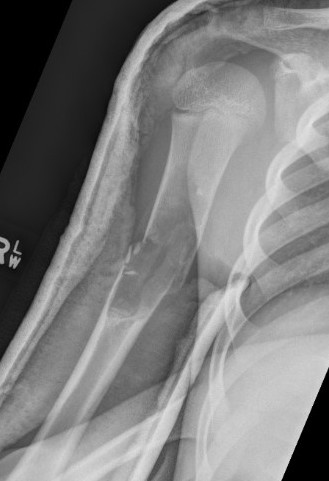

X-ray

Well-defined lucency

- thin sclerotic rim

- usually central

- thinned cortex with slight expansion

- thin internal septa

- can be multi-loculated

Fallen-Leaf (AKA fallen-fragment)

- with pathological fracture

- indicates that the lesion has no matrix and is fluid filled

Fallen leaf sign

Fracture

1. Humerus

Typically treat nonoperatively

Obtain union

Consider further intervention when fracture heals and UBC persists